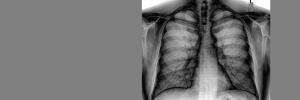

Suid-Afrika het in 2016 die hoogste voorkoms van TB in die wêreld gehad, met 781 per 100 000 bevolking. TB is ook die hoof oorsaak van sterftes in die land.